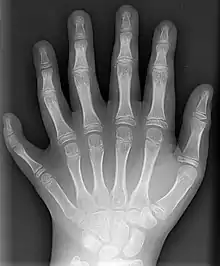

- (Nosologie) Malformation d’origine congénitale, se caractérisant par l’existence d’un doigt surnuméraire.

Les deux mères ont été examinées par notre consœur médecin du travail, et elle n’a pas retrouvé d’hexadactylie chez elles.

— (Concours médical, volume 123, numéros 34 à 40, 2001)